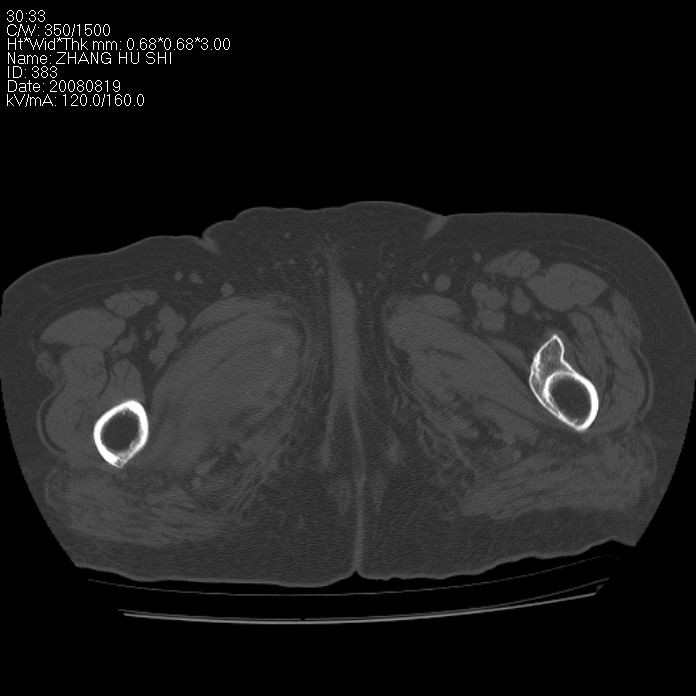

标题: CT15287:女 93岁 右髋关节疼痛 原左侧粗隆间骨折 CT发现右耻 [打印本页]

标题: CT15287:女 93岁 右髋关节疼痛 原左侧粗隆间骨折 CT发现右耻

支持转移并周围软组织侵犯右闭孔内肌侵犯,但tb不能完全除外。

耻骨软骨肉瘤可能性大